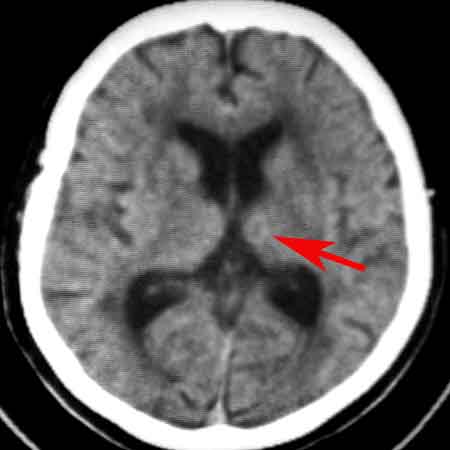

标题: CT8860:陈旧性脑出血

女81岁,头晕、流延。

1:支持左侧丘脑脑出血吸收演变

1、左丘脑区脑出血吸收期改变。

考虑:1、左丘脑区脑出血吸收期改变。

2、皮层下动脉硬化性脑病伴脑萎缩。

时间已经一年,不可能是单纯血肿吸收,如果是应该是软化灶,周围不应该有环行高密度影,应该行增强扫描,看是否是肿瘤并出血,出血吸收,肿瘤存在,或后来合并炎症病灶.

1 皮层下动脉硬化性脑病伴脑萎缩(无争议)

2 左丘脑区脑出血吸收期改变(有争议),一年出血已吸收,应为软化,边缘环形壁可能是胶质增生所致。